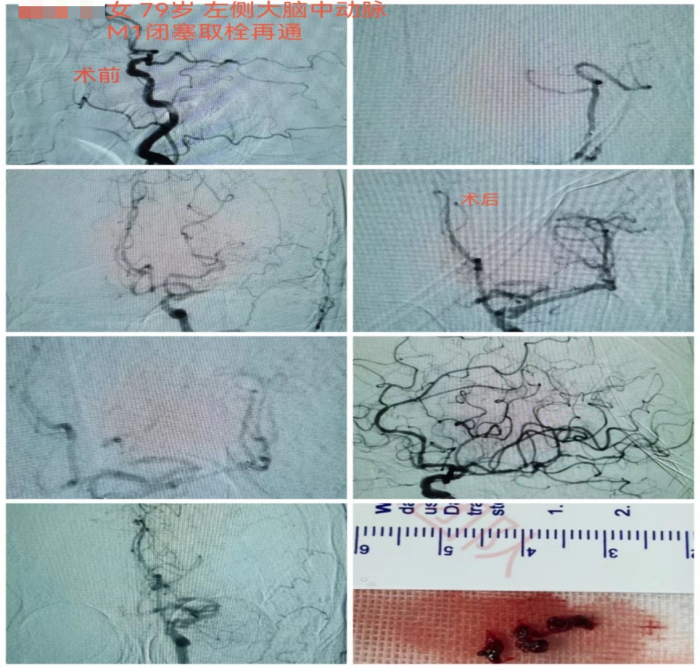

9时左右,家属将蒋奶奶送至长沙市融城医院,行头部CT和MRI后考虑左侧大脑中动脉闭塞引起的脑梗死,需立即接受动脉取栓治疗。长沙市融城医院立即联动长沙市中心医院(南华大学附属长沙中心医院)高级卒中中心,启动卒中绿色通道。

12时24分,“120”救护车到达长沙市中心医院(南华大学附属长沙中心医院)急诊,立即完善头颅CTA提示左侧大脑中动脉M1段栓塞。监测生命体征以及复查必要检查项目后,神经内科副主任医师冯铁桥与患者家属沟通病情及手术相关事项,签字后患者被转入早已做好准备的介入导管室,行“左侧大脑中动脉闭塞急诊介入开通术”,施行动脉取栓。

12时45分,患者被推进介入导管室,此时患者仍处于颅内大血管闭塞动脉取栓的黄金时间窗内(6小时),救治工作紧张有序地展开。10分钟后股动脉穿刺成功,患者的取栓血管通路顺利建立。

13时33分,患者闭塞的血管被开通,缺血的脑组织恢复有效的血流灌注。术后,患者血管再通良好,闭塞远端血流较前明显改善。患者右侧肢体肌力明显较发病时好转,能简单发声、听懂对话。

第二天,患者能自行下地行走,语言功能也得到恢复。从卒中发病到完成介入取栓治疗,蒋奶奶的“生死时速”过程历经6小时40分钟。